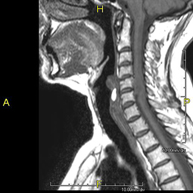

- RM Columna cervical

Prueba diagnóstica no invasiva que consiste en la obtención de imágenes de alta definición anatómica de la columna cervical mediante el empleo de un campo electromagnético y ondas de radio (con un emisor y un receptor). No utiliza radiación ionizante. Indicaciones: traumatismo, degeneración de la columna, hernias.